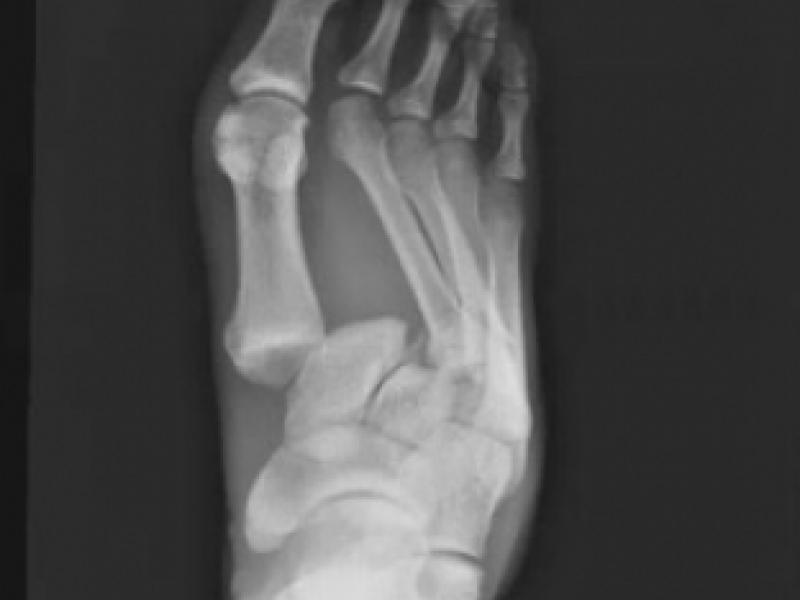

A 25 yo male presents after an MVC with severe right foot